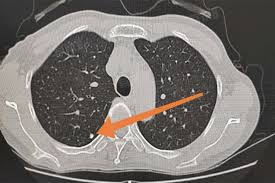

“双肺可见多发小结节影,大小约 2–5mm,边界清晰 / 模糊不等。”

当结节直径 ≤6mm 时,称为“小结节”或“微结节”;

“多数 3–5mm 小结节都是良性的炎症残影。真正需要关注的,是那些‘单侧、毛刺状、在短期复查中长大的’结节。”

成年人胸部CT发现小结节的概率约为 20%–50%;

其中超过90%是良性(炎症、纤维化、钙化灶等);

仅不足5% 需要进一步干预或手术。